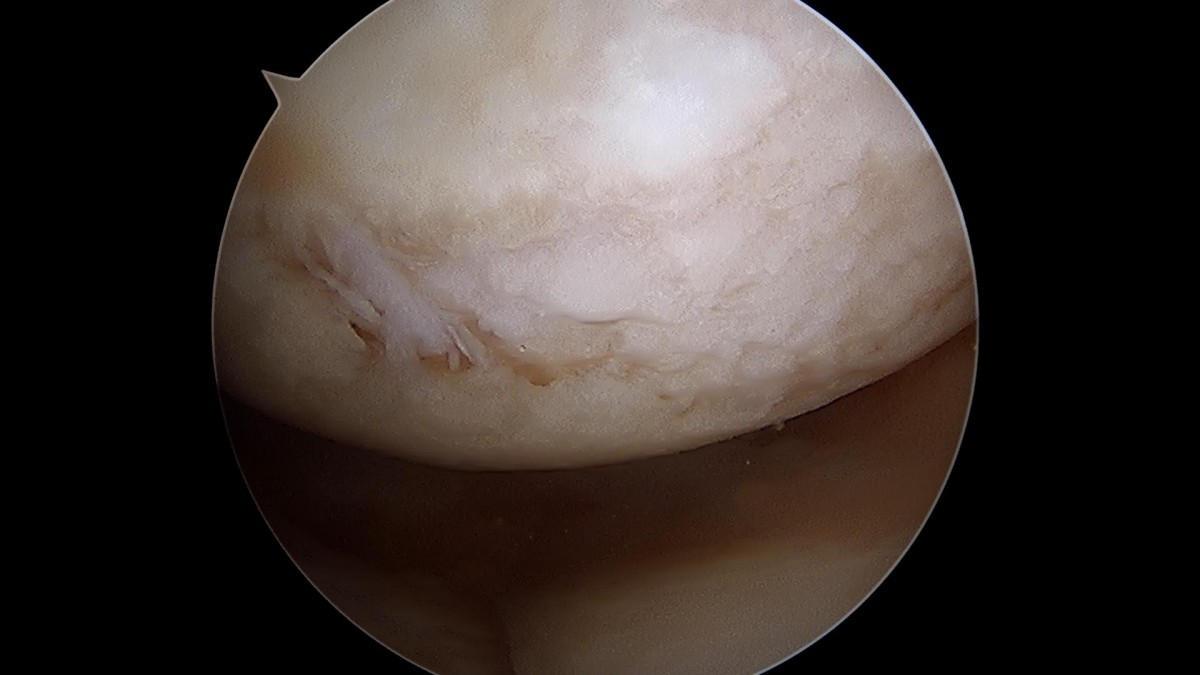

배우한원장님 무릎 반월상 연골판 파열 수술 (782)염광O 환자

작성자 최고관리자 댓글 0건 조회 1,058회 작성일 22-02-23 12:40